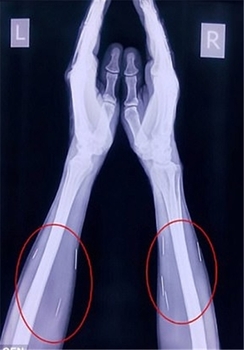

این مرد هندوستانی که «بادریلال مینا» نام دارد و در ایالت راجستان زندگی میکند، 75 سوزن در گردن، دستها و پاهایش وجود داشت.